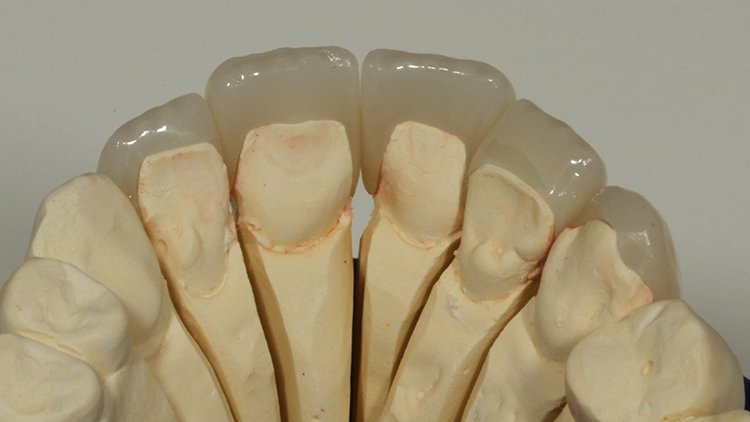

Bei der jetzt anstehenden Teilkronen- bzw. Veneerversorgung der Zähne 12 bis 23 blieb zunächst die Frage des keramischen Restaurationsmaterials zu klären. Neben der bewährten und hochästhetischen glasbasierten Keramik [2,8,10,14–16] eignen sich heutzutage transluzente Zirkonoxidmaterialien hervorragend für die ästhetische Ausgestaltung von Frontzahnbereichen [11], da sie genauso gut verklebt werden können wie Glaskeramiken [9,23].

Gerade im Bereich parafunktional gefährdeter Areale punktet das gegenüber der klassischen Glaskeramik doch deutlich bruchfestere Vollzirkonmaterial. Da bei der Patientin bereits mehrfach Füllungen und Inzisalkanten frakturierten, fiel in diesem Fall die Materialauswahl auf ein hochtransluzentes, polychromes Vollzirkon (zolid fx multilayer, Amann Girrbach), welches mit Ceramotion ZR (Dentaurum) verblendet wurde. Hergestellt wurde die Arbeit (Abb. 10 und 11) im eigenen Meisterlabor durch ZTM Richard Bohrer.

Prof. Dr. Ernst